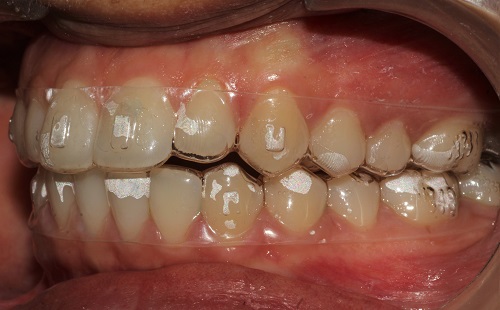

The various treatment offered in the department includes fixed orthodontic treatment with metal, ceramic,self-ligating brackets, treatment with mini-implants, Rapid Maxillary Expansion appliances, orthognathic surgeries to correct facial deformities, distraction osteogenesis procedures with Internal and External distractors, treatment of cleft lip and palate, Pre-surgical Naso Alveolar Moulding on cleft cases, Fixed functional treatment with Forsus, Powerscope, Herbst etc, Lingual Orthodontic treatment, Myofunctional Appliance Therapy, Aligner Orthodontic Treatment ,Myofunctional trainers, Splints- For Temporomandibular joint disorders as well as Class III correctors in growing individuals with appliances such as Tandem Traction Bow Appliance.